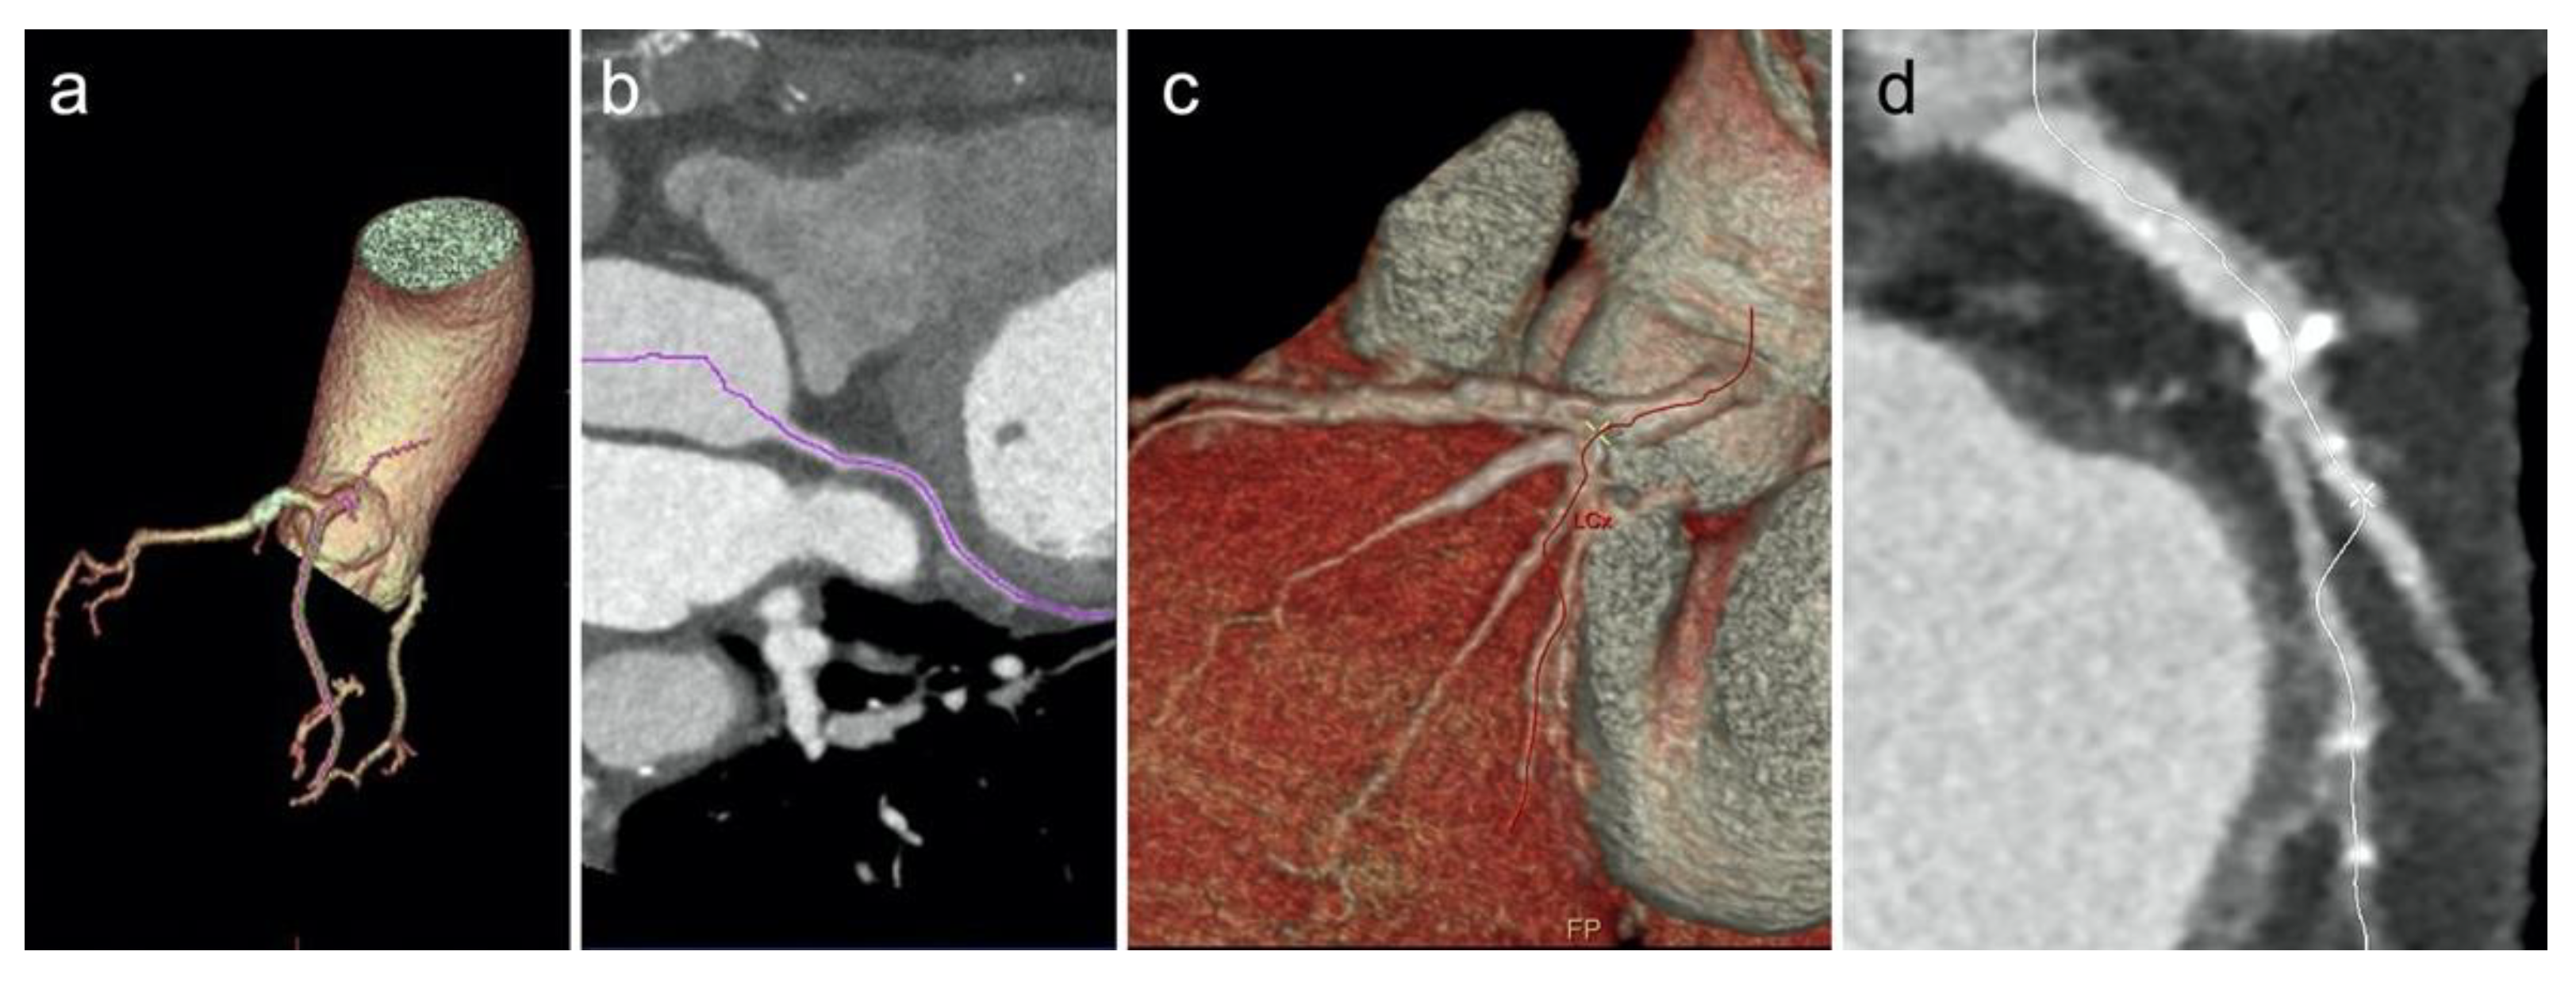

2.3. Image Post Processing—Group 1

2.5. Image Post Processing—Group 2